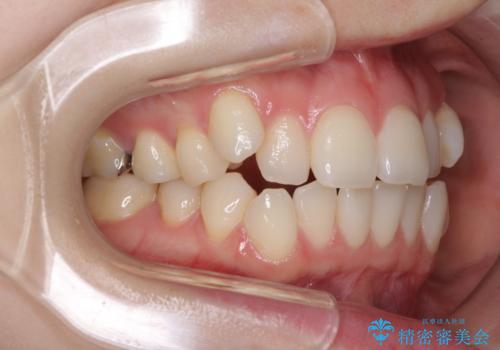

前歯のデコボコをインビザラインで改善

- 前歯のデコボコや八重歯の様になっていることを気にして来院された患者様です。

犬歯捻れて前方に飛び出しており、下顎前歯もそれに沿うようにデコボコとなっていました。

IPR(歯と歯の間を削る処置)によりスペースを獲得して上下顎前歯のデコボコを改善し、前歯が前方に突出しないように設定した上で、インビザラインにて矯正治療を行うこととしました。